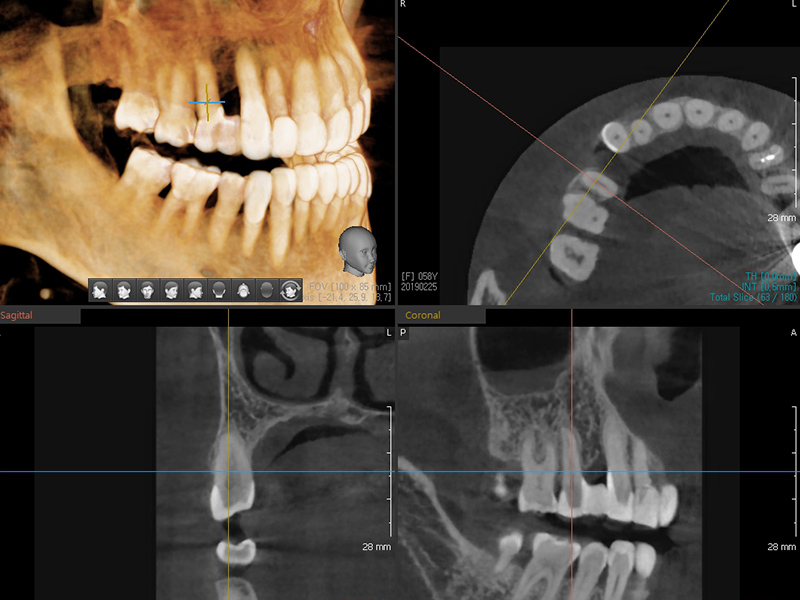

사랑니 상태별 진단

• 매복된 사랑니

아직 자라지 않았거나, 머리 부분만 자란 사랑니는 간혹 치아를 둘러싸고 있는 치아주머니에 물이 차

염증반응을 일으키기 쉽기 때문에 눈에 보이지 않더라도 발치하는 것이 좋습니다.

• 기울어진 사랑니

사랑니 바로 앞 어금니를 간섭해, 충치가 발생할 확률이 매우 높고 이로 인해 치열이 불규칙해 질 수 있습니다.

• 누워서 가로로 자란 사랑니

주변치아의 충치와 염증을 유발하기 쉽고, 턱뼈에 압력을 가해 지속적인 통증을 유발하거나,

턱뼈가 약해질 수 있습니다.

• 곧게 자란 사랑니

정상적으로 자란 사랑니는 관리만 잘해주면 괜찮을 수 있지만, 충치나 잇몸질환이 발생하기 전에

미리 발치하는 것이 더 좋습니다.